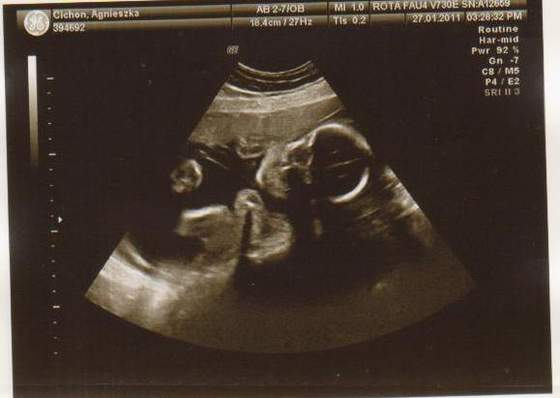

cześć dziewczyny to i ja chciałabym do Was dołączyć, właśnie znalazłam to forum. Mieszkam w Irlandii od 4 lat i mam synka 21 miesięcy, a teraz jestem w 28 tc bliźniaczej :-) dwie dziewczynki dwujajowe :-) też mnie trochę przeraża poród bliźniaków ale trzeba jakoś urodzić ;-) Pierwszy poród miałam jak marzenie szybko, sprawnie i nawet bez znieczulenia, mam nadzieję że i tym razem bęzie podobnie.

Hej podwojne mamunie:-)Ja juz rozpakowana dawno mamusia dubeltowka.Gratuluje wam serdecznie i witam w gronie tych wybranych hihiNiczego sie nie bojcie.Ciaxa blizniacza jest pod specjalna opieka.Czekaja was czeste wizyty w szpitalu i czeste ogladanie maluszkow na usg :-)